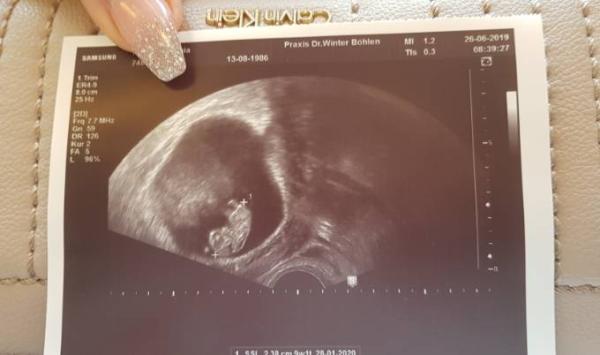

Guten Morgen ihr lieben bevor ich in meinen 9 Stunden Arbeitstag Starte, wollte ich euch Berichten wie es heute morgen beim FA war. Unserm Krümel geht es bestens. Toll gewachsen alles fein bin jetzt wieder in der normalen Woche so wie ich es eigentlich auch ausgerechnet habe ...letztens war ja laut US 2.2. Termin jetzt ist es wieder der 28.1.2020 aber ich glaube das wird sicherlich immer wieder mal + und - anzeigen Eisen Tabletten hab ich verschrieben bekommen und nächste Woche Mittwoch bekomme ich meinen Mutterpass also uns geht es gut...bis auf die üblichen Schwangerschafts Beschwerden und diese Hitzeeee Habt einen tollen Tag und passt auf euch auf...viel Trinken bitte Bildchen vom Krümel ach sind wir verliebt

Bild zu zurück vom FA - Forum für Januar - Mamis